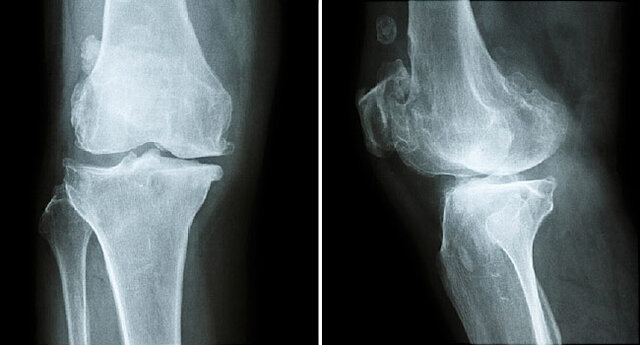

محققان هشدار دادند خواب ناکافی با کاهش تراکم استخوانی و خطر ابتلا به عارضه پوکی استخوان مرتبط است. پوکی استخوان بیماری است که موجب ضعیف شدن بافت استخوانی شده و خطر شکستگی را افزایش میدهد. در این شرایط حتی حوادث بسیار سطحی میتواند موجب شکستگی استخوان شود.

به گزارش اندی تیوی، در این بررسی اطلاعات ۱۱ هزار و ۸۴ زن مورد مطالعه قرار گرفت که مدت زمان خواب آنان در طول شبانه روز پنج ساعت یا کمتر بوده است. محققان اطلاعات این افراد را با زنانی مقایسه کردند که هفت ساعت در شب میخوابند. یافتههای بدست آمده نشان داد که خواب ناکافی با کاهش حجم تراکم استخوانی همراه است.